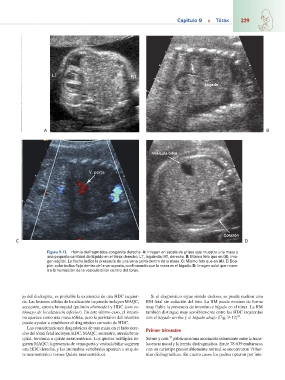

Figura 9-13. Hernia diafragmática congénita derecha. A: Imagen en escala de grises que muestra una masa y

una pequeña cantidad de líquido en el tórax derecho; LT, izquierda; RT, derecha. B: Mismo feto que en (A), ima-

gen sagital. La flecha indica la presencia de una vena porta dentro de la masa. C: Mismo feto que en (A). El Dop-

pler color indica flujo dentro de la vena porta, confirmando que la masa es el hígado. D: Imagen axial que mues-

tra la herniación de la vesícula biliar dentro del tórax.